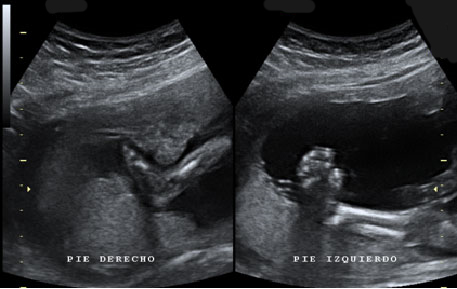

Imagen ecográfica de pie zambo o equinovaro

En la imagen superior se ven los dos pies de un feto, en el lado izquierdo un pie bien orientado con la pierna y en el lado derecho un pie con una desviación anómala, denominada pie equinovaro o zambo.